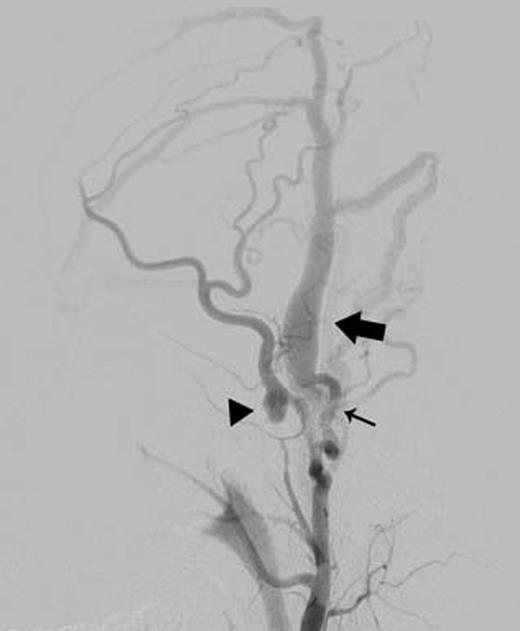

A 24-year-old male was admitted to our hospital after a traffic accident. Computed tomography scan had shown an acute epidural hematoma on the right surface of frontal lobe, which was emergently treated by surgical evacuation. One month later, he began to complain of pulsatile tinnitus in the left ear. A head magnetic resonance angiogram showed an extremely dilated vein in the left temporal region (Fig. 1). An angiography revealed a direct shunt between the left parietal branch of the STA and the superficial temporal vein (STV) in the preauricular region as well as an aneurysm in the left frontal branch of the STA (Fig. 2). He underwent surgery to remove the AVF and the aneurysm (Fig. 3). Pulsatile tinnitus disappeared immediately after surgery. Histopathological examination demonstrated that the artery was connected to the vein through the thin-walled vessels lacking internal elastic lamina and muscularized media, suggesting that the connecting vessels were newly formed (Fig. 4).

Left external carotid arteriography showed a high-flow AVF from the parietal branch of the STA (thin arrow) to the STV (wide arrow), and an aneurysm on the frontal branch of the STA (arrowhead).